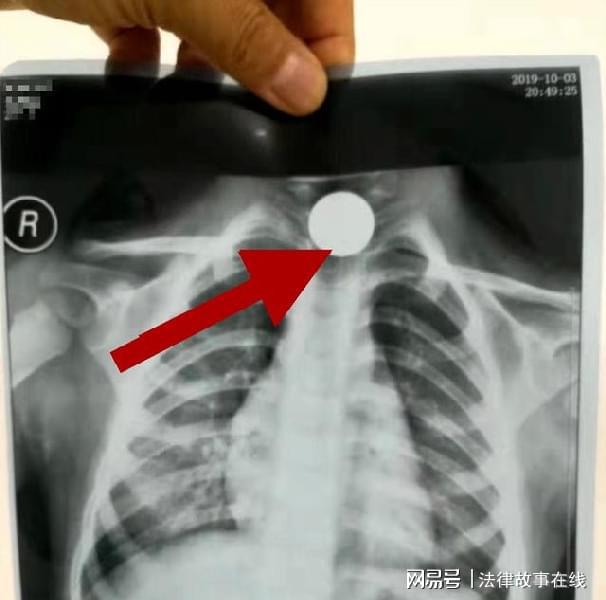

一位4岁女童,误将一枚五角的硬币吞食,家长发现她哭闹不止,捂着肚子,这才询问得知女儿吞食的硬币,吓得爸妈连夜赶去了医院治疗。

医生商量后决定手术取出硬币,术前为了再次确认硬币的位置,又让家长带去排了个片,谁知道医生拿到片子以后却摇摇头说:“做手术也取不出来了。”

原来,这会硬币已经由原来的食道转移到了消化道,现在就算开刀动手术也没办法将硬币取出来,只能通过孩子的消化功能自行排出体外。